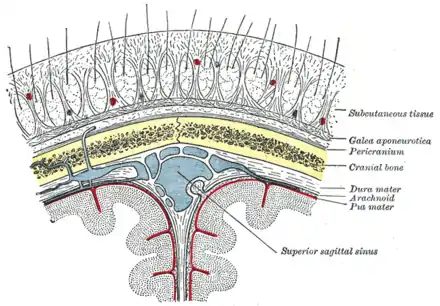

Une coupe des différents méninges.

Coupe coronale de la branche inférieure (corne temporale) d'un ventricule latéral. Représentation schématique d'une coupe du haut du crâne, montrant les membranes du cerveau.

Représentation schématique d'une coupe du haut du crâne, montrant les membranes du cerveau. Coupe schématique du cuir chevelu.

Coupe schématique du cuir chevelu.